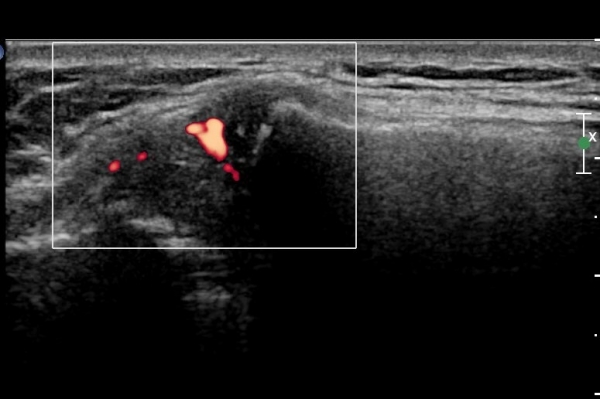

¿ìÃø Èä°ñ¼â°ñ°üÀýÃÊÀ½ÆÄ°Ë»ç¿¡¼­ °üÀýÀÇ ÅðÇ༭ º¯È­°¡ °üÂûµÊ(»çÁø 3, 4).

ÆÄ¿öµµÇ÷¯°Ë»ç¿¡¼­ °üÀýÀýºÎÀ§ Ç÷·ùÁõ°¡°¡ °üÂûµÊ(»çÁø 5).